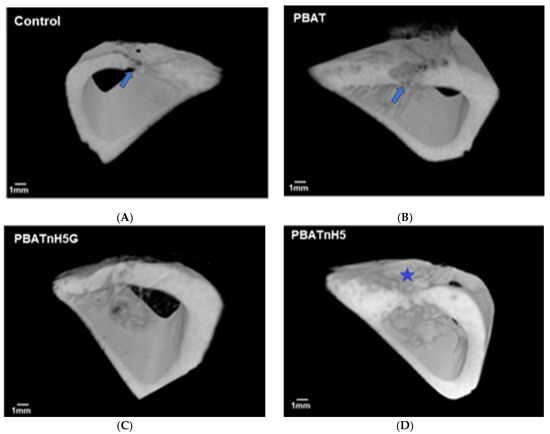

2.4.3. Microcomputed Tomography

2.4.4. Analysis of Bone Remodeling